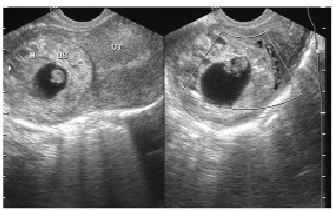

宫角妊娠的超声诊断与鉴别分析--中国期刊网

【摘要】目的探讨宫角妊娠的超声声像图特点。方法回顾分析手术及病理已证实的30例宫角妊娠的超声声像图特点。结果根据超声声像图表现,宫角